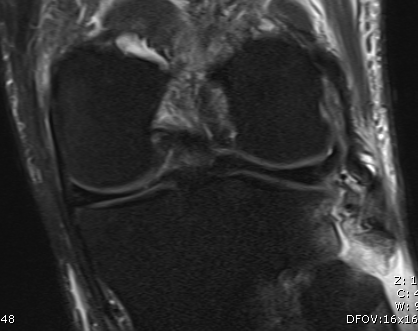

MRI

Lateral collateral ligament anatomy

Don't see entire length on single MRI

- use coronal to look for origin from lateral epicondyle above popliteal insertion

- use coronal to look for insertion onto anterolateral fibular head

Normal anatomy

Midsubstance tear of LCL

Popliteus anatomy

Don't see entire length on single images

- coronal image to see insertion onto popliteal fossa below LCL

- follow tendon around on coronal images

- watch as becomes musculo-tendinous (can often be torn here)

- muscle inserts onto posteromedial tibia

Normal anatomy